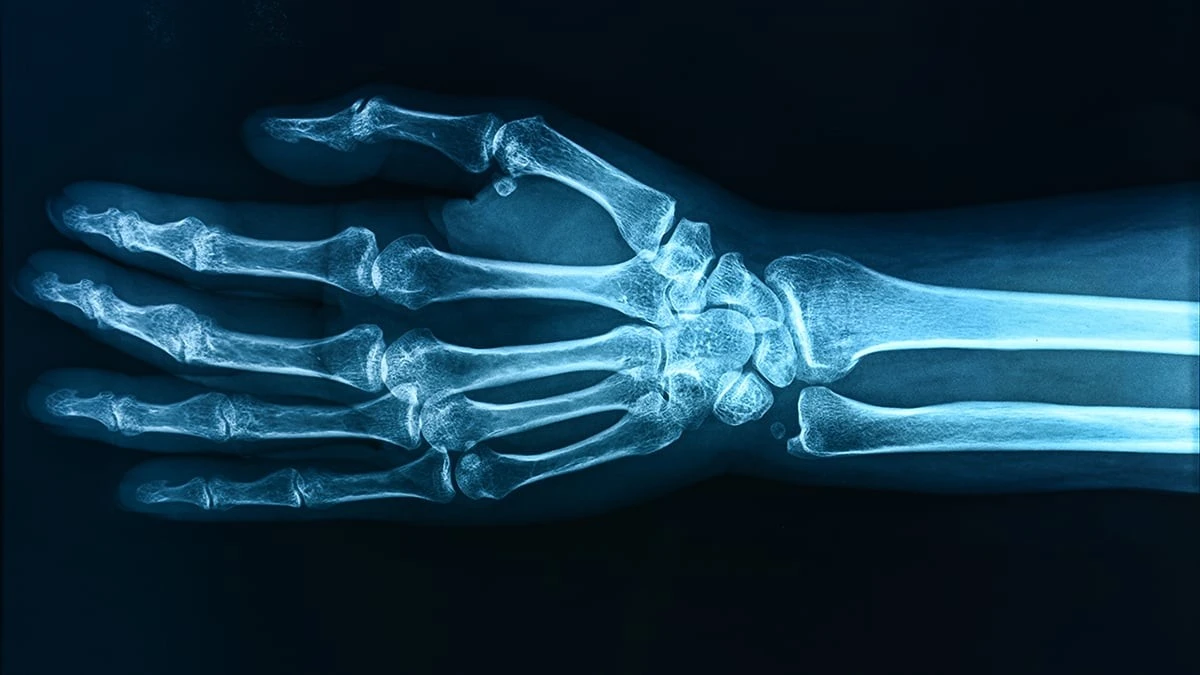

Tým odborníků sledoval 218 dětí a zjistil děsivou souvislost: vyšší hladina látky PFOA v krvi přímo souvisí s nižší hustotou kostí v předloktí kolem 12. roku života. A co je ještě zajímavější (a smutnější), u dívek byl tento negativní dopad mnohem výraznější než u chlapců.

Rozdíl mezi nejnižší a nejvyšší hladinou těchto chemikálií může znamenat až o 30 % vyšší riziko zlomenin. Představte si to jako stavbu domu – když v základech ušetříte na materiálu, celá konstrukce bude v budoucnu labilní. Stejně tak kosti, které nezesílí v dětství, vedou k osteoporóze v dospělosti.

Jak tyhle chemikálie „vypínají“ kosti

Možná si říkáte, jak může kousek teflonu ovlivnit kostru? Mechanismus je pravděpodobně skrytý v narušení vitaminu D. Tyto chemikálie působí jako filtr, který tělu brání správně využívat „déčko“, bez kterého se vápník do kostí prostě nedostane. Je to jako mít kávový filtr, který nepropouští kofein – pijete kávu, ale efekt nikde.